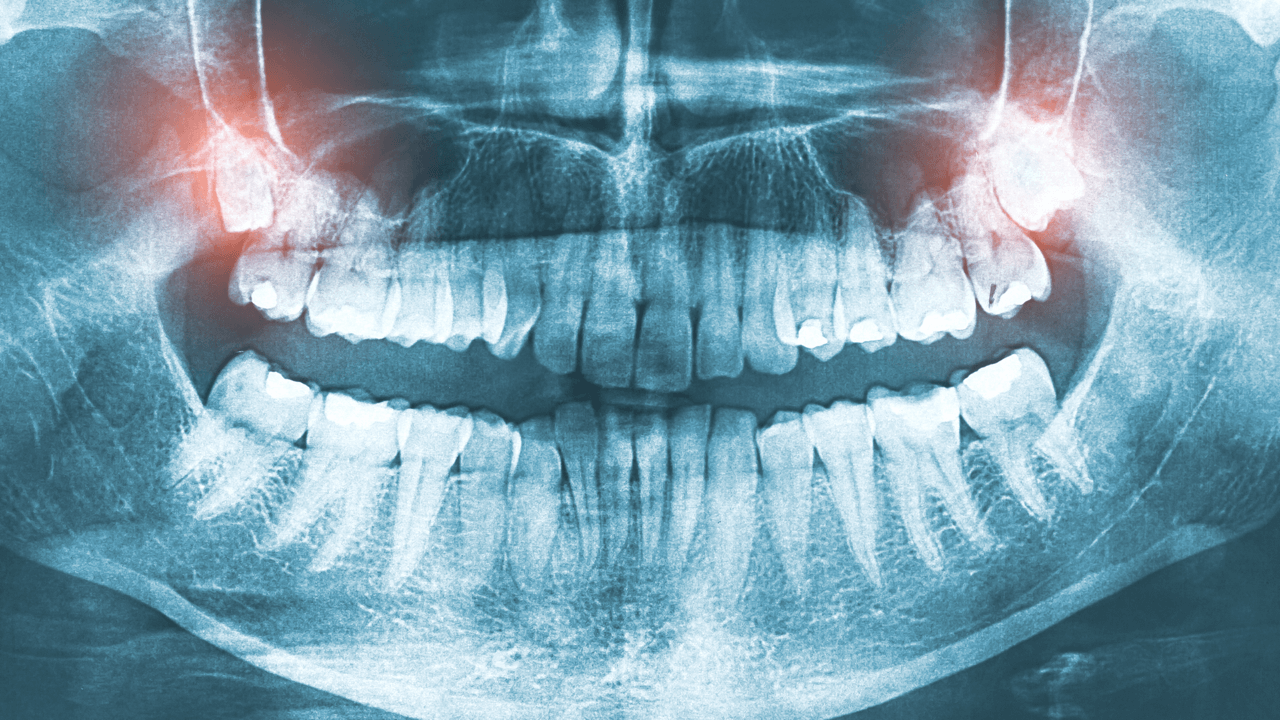

W tym miejscu zaznaczamy, że odpowiednia diagnostyka zębów zatrzymanych (np. zdjęcia rentgenowskie) pomaga rozpoznać ich nieprawidłowe ułożenie i w zależności od stopnia skomplikowania konkretnego przypadku – zaplanować oraz wdrożyć leczenie.